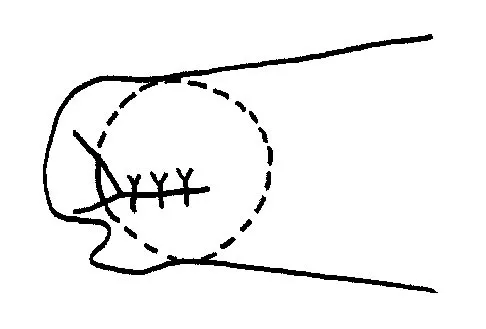

A 60-year-old patient had the procedure shown in Figure 7 performed 5 years ago. When converting this patient to a total knee arthroplasty (TKA), what patellar problem is commonly encountered intraoperatively?